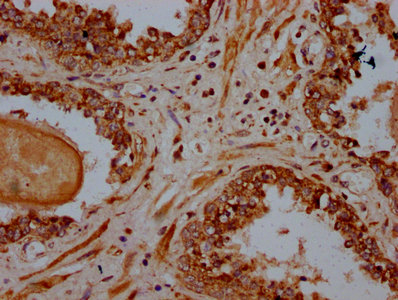

IHC image of CSB-PA618917LA01HU diluted at 1:600 and staining in paraffin-embedded human prostate cancer performed on a Leica BondTM system. After dewaxing and hydration, antigen retrieval was mediated by high pressure in a citrate buffer (pH 6.0). Section was blocked with 10% normal goat serum 30min at RT. Then primary antibody (1% BSA) was incubated at 4°C overnight. The primary is detected by a biotinylated secondary antibody and visualized using an HRP conjugated SP system.